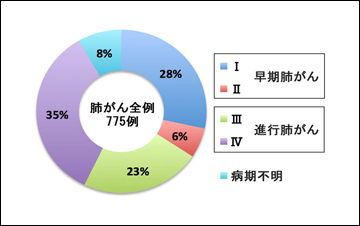

2007~2011年の5年間に当院において診療した肺がん患者の総数は775名(男性524名、女性251名、平均年齢70.8歳)でした(図1)。検査の結果から全患者の約34%が早期肺がんでしたが、残りの66%は進行肺がんと診断されました(図2)。775名中246名(全体の32%)が手術療法(外科的切除術)を受けました。手術を受けた患者のうち41名(手術患者の17%)は再発予防の抗がん剤投与による追加治療を受けました。残りの529名(68%)は、抗がん剤治療、放射線治療、緩和治療を単独または組み合わせて治療を行いました。手術療法を受けた患者と受けなかった患者の病期内訳を、それぞれ(図3)のA、Bに示しました。

図2 当院肺がん全症例における病期内訳(2007~2011年)